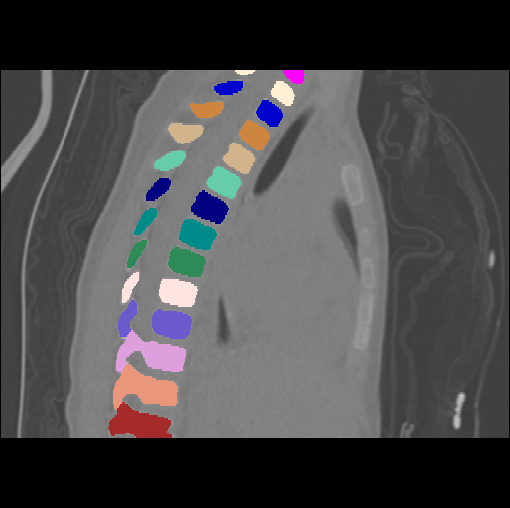

Images

GT

Predictions

We calculate the two metrics of each vertebra, and the results are reported in Table 2. On the one hand, our experimental results are close to those reported in reference (Sekuboyina et al., 2020) with the same model (nnUnet), verifying the high quality of our annotations. On the other hand, Table 2 shows it is difficult to segment the diseased vertebrae (the DSC of L6 is almost 0). Specifically, the existence of L6 confuses the model, resulting in prediction dislocations (see the last row in Fig. 4). Thus, our labeled dataset, which contains many L6 cases, is very valuable for the diseased vertebrae segmentation (we have stated those cases that are hard for annotation in the readme.txt file). Table 2 illustrates that the model trained with our annotations can achieve good performance on our CTSpine1K dataset but a much worse performance on the VerSe Challenge datasets, which explains there is an obvious domain gap between our annotated dataset and the public dataset. We infer the reason is that the COlONOG dataset is based on an empty stomach and colon, confusing the deep learning model by the changes of air content in the abdomen (see Fig. 3). Therefore, our annotations are a good complement to the existing datasets.

3.2.2 Qualitative results.

Some visualization results are presented in Fig. 4, where we can observe that the baseline model can achieve excellent segmentation results. Nevertheless, some failed predictions occur when spinal diseases exist, especially sacral lumbarization and lumbar sacralization. Besides, the image’s resolution of Z direction is closely related to the results, and a lower resolution leads to worse results. Maintaining a reasonable performance for a low resolution is a research challenge. Image superresolution (Peng et al., 2020) might be worth exploring.